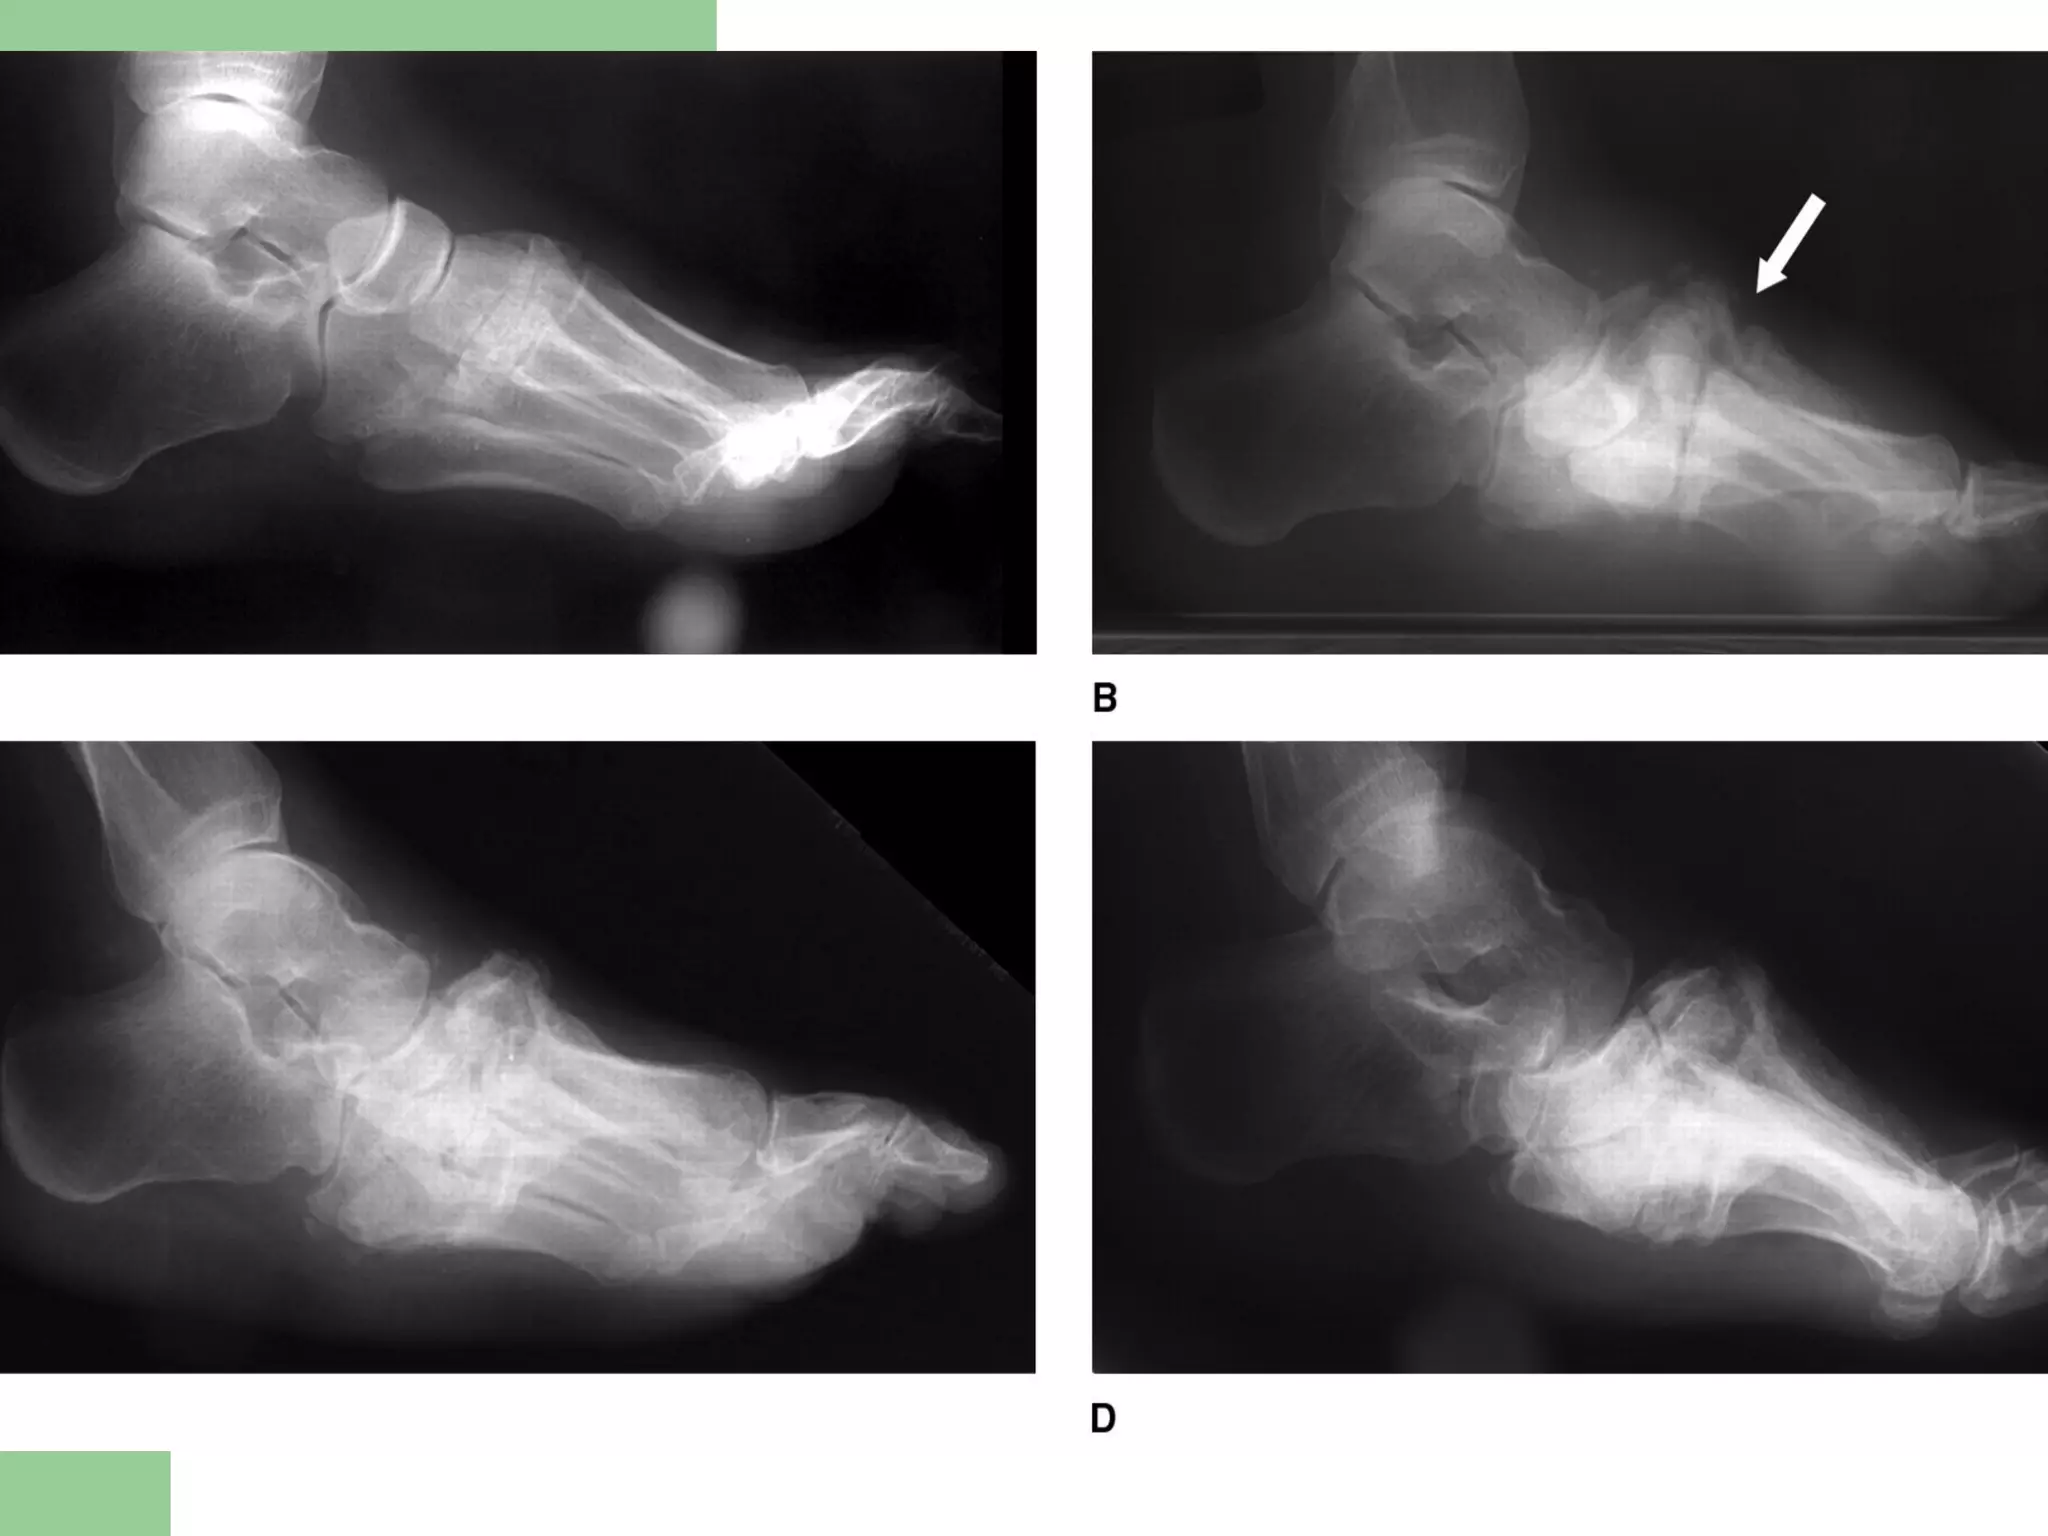

Radiographic Staging

(Eichenholtz, 1966)

 I Developmental (acute) stage

 II Coalescence (quiescent) stage

 III Consolidation (resolution) stage

Eichenholtz Classification

 Stage I - Developmental (acute)

– Hyperemia due to autonomic neuropathy weakens

bone and ligaments

– Diffuse swelling, joint laxity, subluxation, frank

dislocation, fine periarticular fragmentation, debris

formation

 Stage II - Coalescence (quiescent)

– Absorption of osseous debris, fusion of larger

fragments

– Dramatic sclerosis

– Joints become less mobile and more stable

– Aka the “hypertrophic”, or “subacute” phase of

Charcot

 Stage III - Consolidation (resolution)

– Osseous remodeling

– for clinical purposes, stage I is regarded as the

acute phase, while stages II and III are regarded

as the chronic or quiescent phase

Radiographs

 Stage III